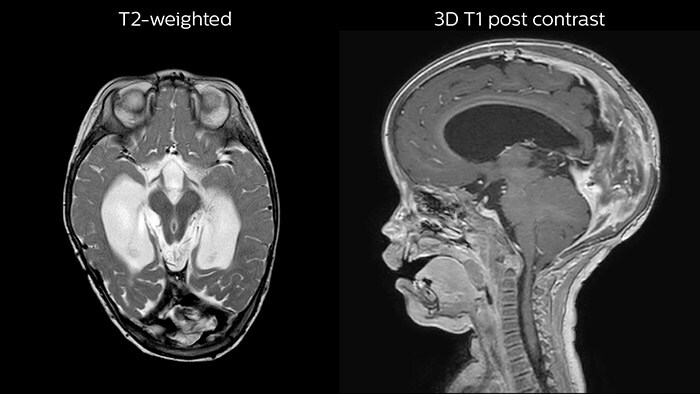

Since scan times of 3D scans can be significantly shortened thanks to Compressed SENSE, the MRI team is performing more 3D scans than before. “The advantage of 3D scanning is that we capture one high resolution sequence, but we can reconstruct images in any orientation, even after the scan, when looking at the images for diagnosis. Having this ability to view any crosssection we need in high resolution, can make re-scanning unnecessary,” says Dr Junge. “We are currently optimizing our routine head examination to include more 3D scans, including T1- weighted, T2-weighted and FLAIR.”

Rostral meningitis and arachnoiditis Both images are from the same 3D T1-weighted post contrast sequence in a newborn, under treatment.